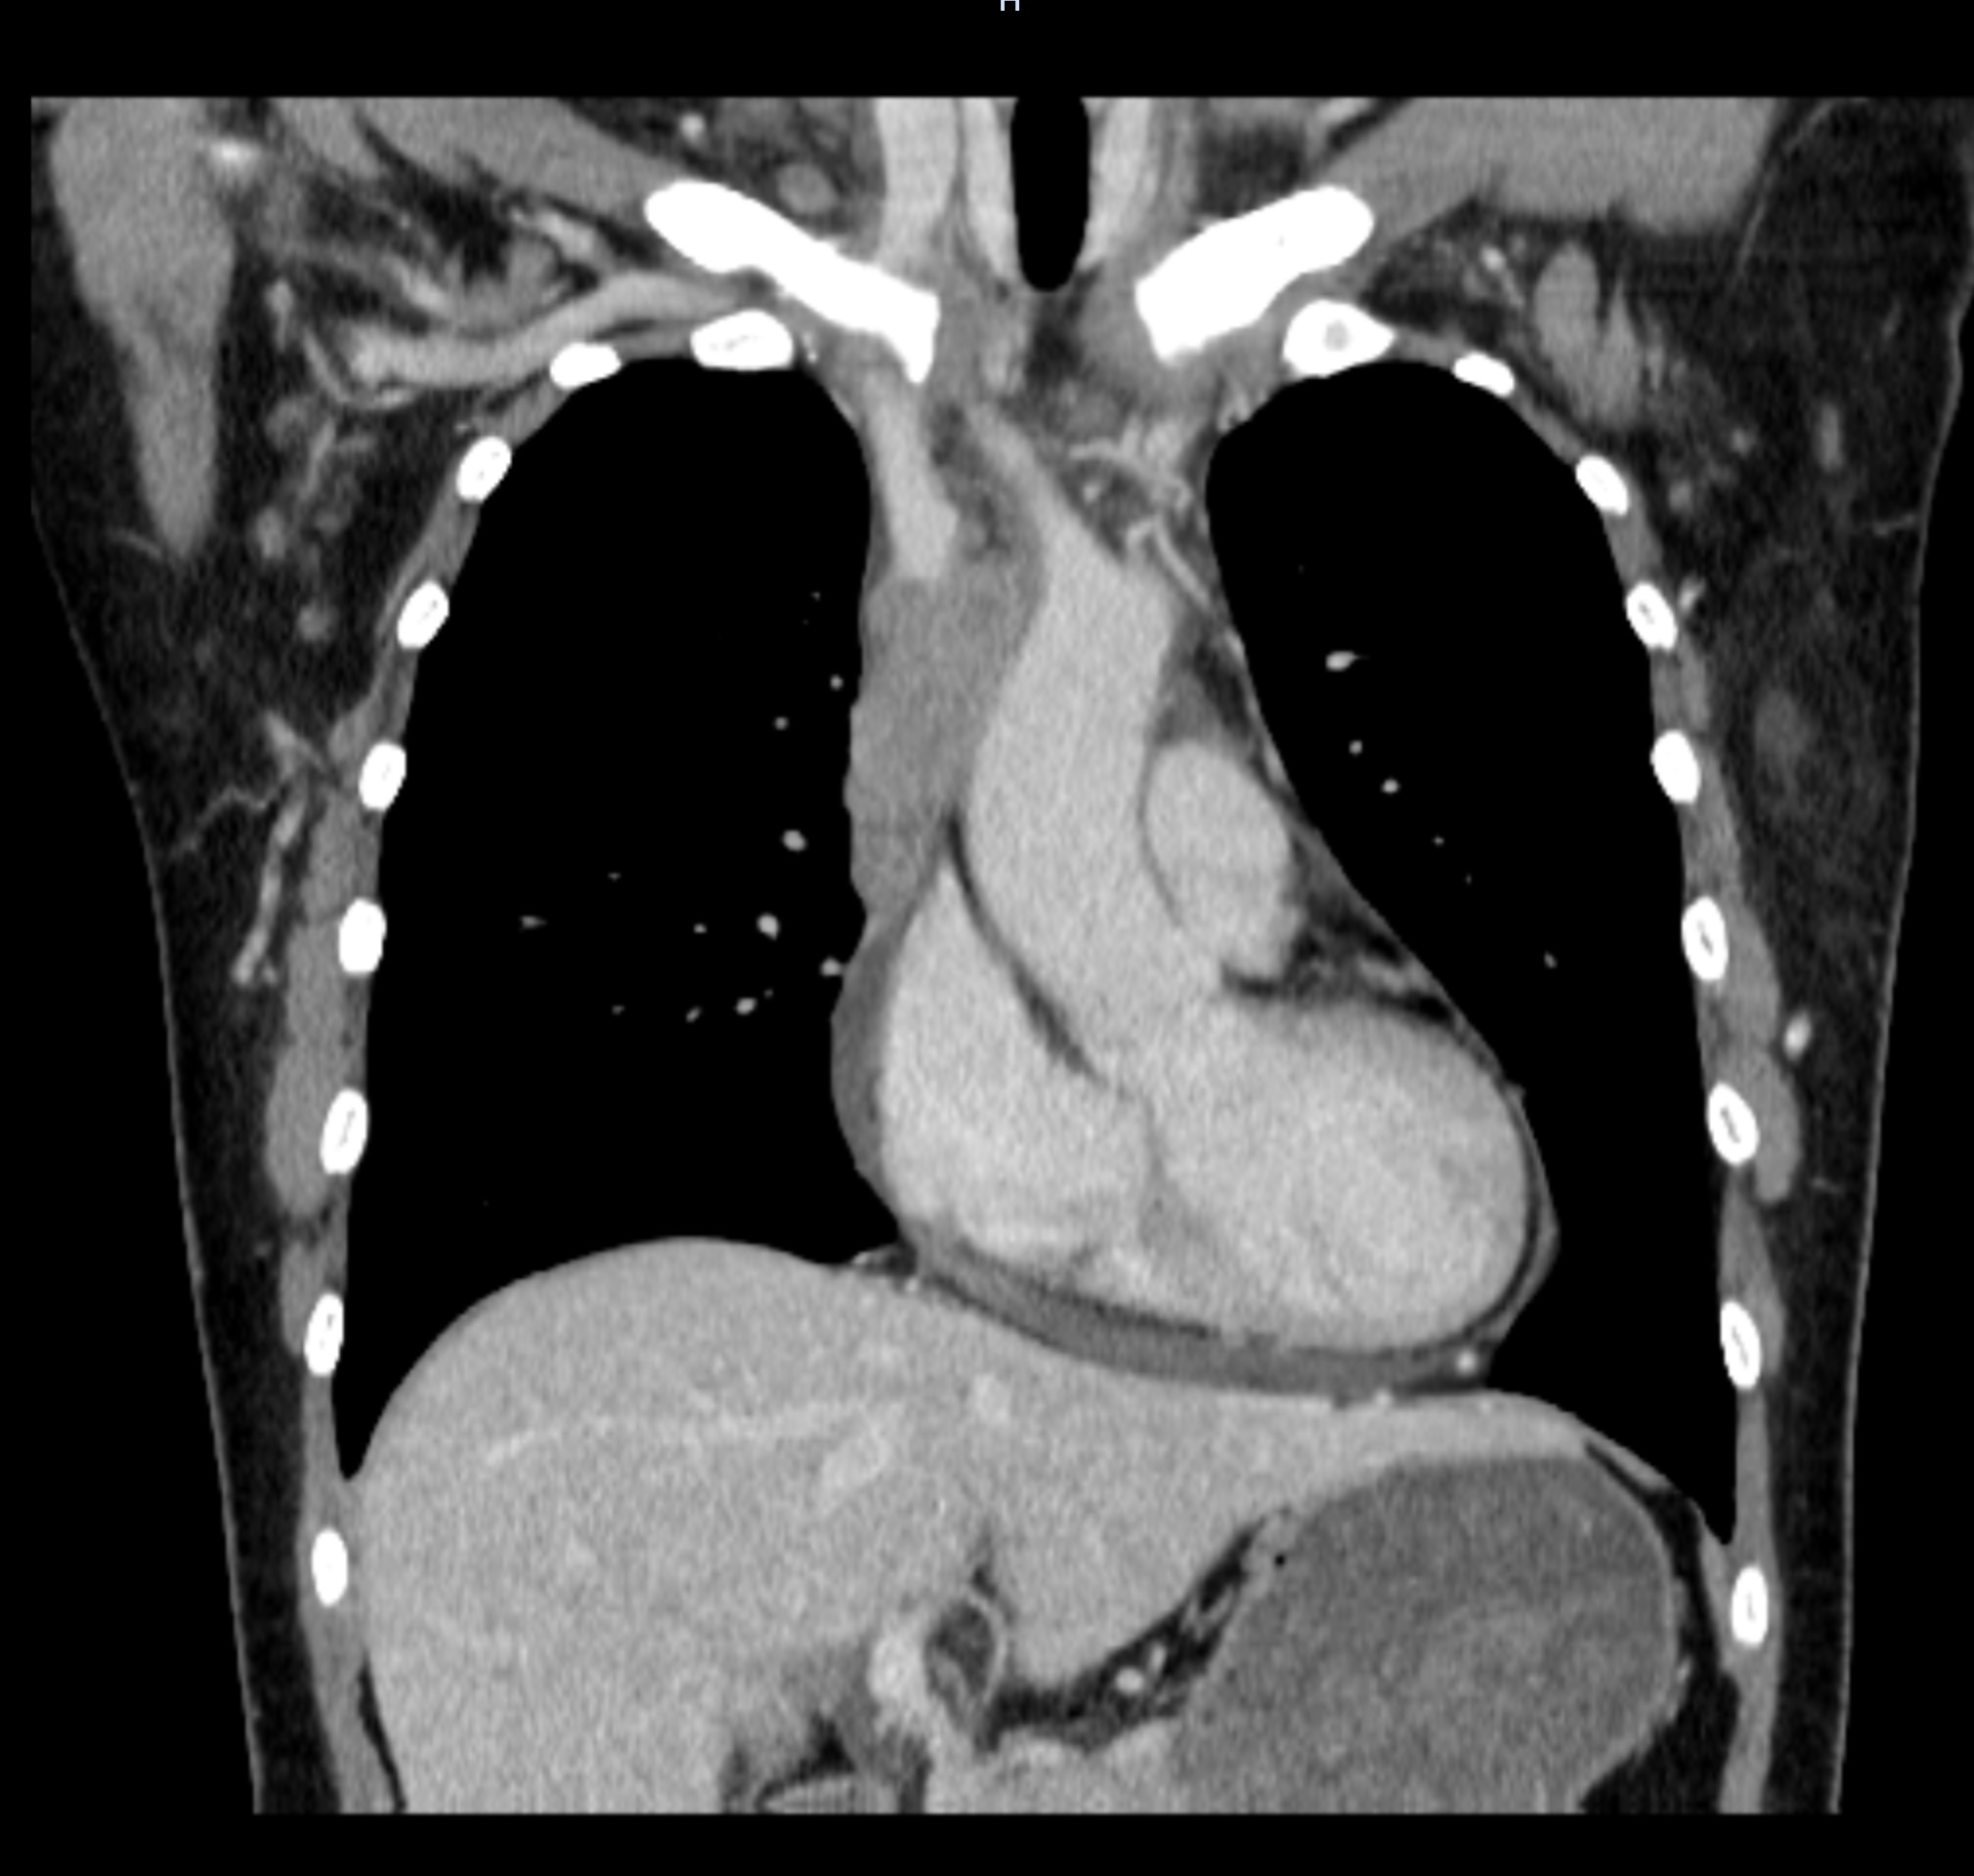

患者术前CT结果提示纵隔肿瘤侵犯上腔静脉及其所有属支

第二天,临桂院区高端256排增强CT检查结果证实了梁恒星主任的诊断——颜女士的纵隔肿瘤很可能是恶性胸腺瘤,并且病变已经外侵,完全阻断了颜女士的上腔静脉,导致上半身、尤其是颅内血液回流受阻,如果不及时手术,可能会出现严重的脑水肿并威胁生命。而恶性胸腺瘤保守治疗效果不确切,不能保证患者能在短时间内解除上半身血流梗阻,一旦决策错误,将带来灾难性后果。